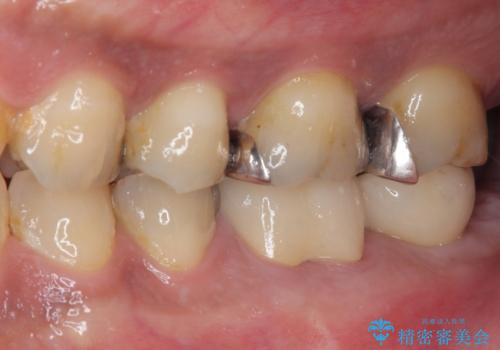

インプラント治療まで待機している間に、手前のむし歯処置されている歯が強い痛みに襲われ、確認したところ、既に神経組織が壊死している状態であったため、根管治療を行い、インプラント部と合わせて補綴治療を行いました。